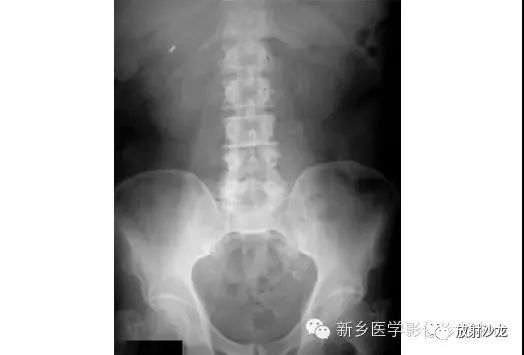

一位67岁腹部疼痛男性。他的腹部平片主要异常是什么?X光片显示肠道气体相对缺乏。在无症状的患者,这往往是正常的变化。在有症状的患者,就像这例患者,当发现当肠襻内充满液体而不是气体,就可以诊断为肠梗阻。其它潜在的腹部无气体的原因在腹水、大型腹部包块、结肠切除术后、急性胃肠炎和肠道缺血。